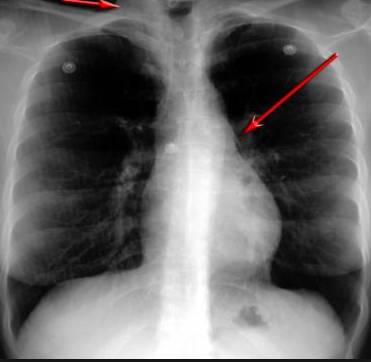

并且,因为呼吸系统结构复杂,在体检时医生很难通过一种检测手段,判定早期患者的病情。

这台4D扫描仪

能让医生有一双可以透视的眼睛

把整个肺部看得清清楚楚!

使用这台扫描仪,将直接把器官变成3D图形!细微的毛细血管,几毫米大的肺泡和支气管,都将能看的一清二楚!

你的每一个气泡,每一段支气管,哪儿有病变都清清楚楚的将展示在医生面前!

也就是说在一切都还没开始恶化前,把这些有问题的器官组织都暴露的一清二楚:

没有这项新技术,医生在做体检的时候,很难通过一种测试断定一个人是否有呼吸系统疾病。

可是现在他们不但能看到整个肺部的3维结构图。还能看到空气进入人体后的所有微小变动!